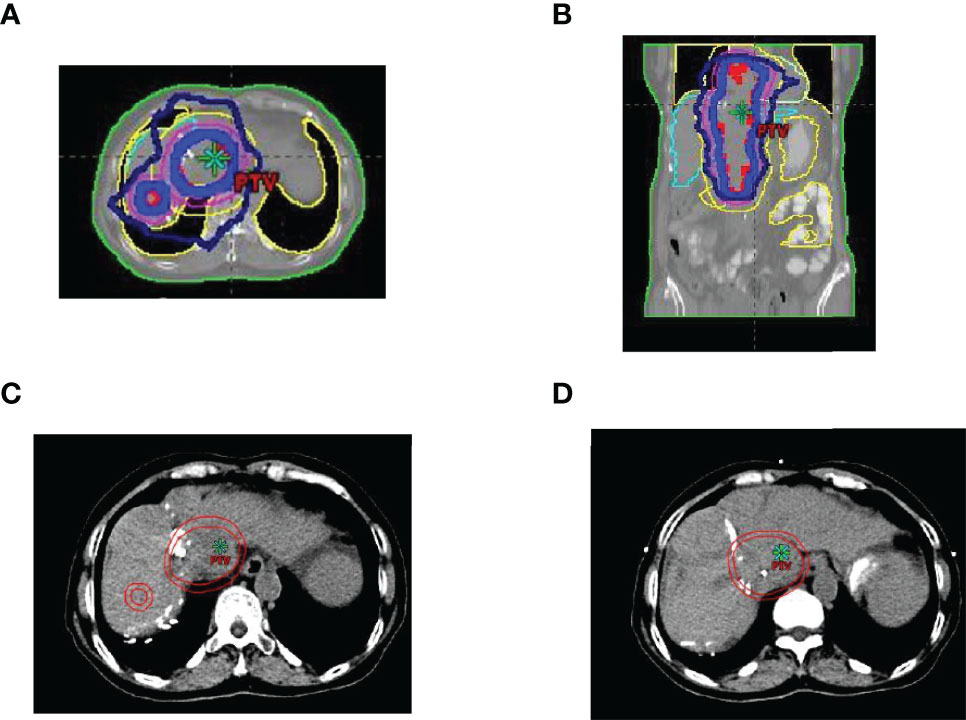

This case report was conducted per the CARE Guidelines (17). In July 2021, a 66-year-old Chinese woman was hospitalized due to severe bilateral lower extremity edema and palpitation, without any accompanying symptoms, such as abdominal pain or bloating. She had no history of high blood pressure, diabetes, or hepatitis. She had been diagnosed with HCC nine years ago and had undergone surgical resection. Postoperative pathology revealed a highly differentiated HCC. She had received radiofrequency ablation because of local HCC recurrence in November 2013 and May 2014. Subsequently, the patient did not undergo medical examination until July 2021. In July 2021, an enhanced computed tomography (CT) showed HCC recurrence at the junction of the anterior segment (S5/S8) of the liver, with approximately 1.8 × 1.4 cm size. The mass wrapped and invaded the adjacent IVC and grew into the IVC, RA, and left renal vein. The diagnosis was HCC with RA and IVC tumor thrombi with Barcelona clinic liver cancer (BCLC) stage-C (Figure 1). Then, the patient received sorafenib treatment and developed grade 4 (the US National Cancer Institute Common Terminology Criteria for Adverse Events [CTCAE v4.03]) skin rash and discontinued the sorafenib treatment. Hormones and proglobulin were used to treat dermatitis, and adverse skin reactions were reversed. According to a published study, radiotherapy can be used to treat liver cancer with RA and IVC tumor thrombi (18). Moreover, immunotherapy plus radiotherapy and antiangiogenic therapy is a safe and effective approach for advanced HCC (19). Therefore, we administrated radiotherapy, immunotherapy, and lenvatinib. The patient received radiotherapy in August 2021 through volumetric modulated arc therapy and respiratory gating technology. The dose for HCC recurrence was 50 Gy/25 fractions and for HCC with RA and IVC tumor thrombi was 45 Gy/25 fractions (Figure 2). She simultaneously received pembrolizumab (100 mg; 2 mg/kg, q3w) and lenvatinib (8 mg/day). Lower extremity edema and palpitations resolved after radiotherapy. Toxicity was well tolerated with no liver toxicity, and grade ≥ 3 adverse events were observed. After four cycles of pembrolizumab plus lenvatinib treatment, the CT scan indicated that the patient had a partial response and a decreased thrombus according to the Response Evaluation Criteria in Solid Tumors (RECIST) v.1.1. The HCC lesion at the junction of S5/S8 segment disappeared, and the IVC/RA thrombus decreased in size (Figure 3). No disease progression was observed. The patient continued to receive the pembrolizumab plus lenvatinib treatment (the last pembrolizumab treatment day was March 26, 2022). The patient remained stable at the time of writing (> 7 months). During the treatment period, there was no grade ≥ 3 adverse events or liver toxicity. Leukopenia (grade 2), thrombocytopenia (grade 1), hypoalbuminemia (grade 1), and hypertension (grade 2) were resolved using symptomatic drug treatment. Granulocyte colony-stimulating factor was administered to deal with white blood loss. A CT scan was regularly performed for every 3 months. Blood routine, liver function, kidney function, electrolyte, thyroid function, and pituitary function were regularly measured. The timeline scheme of the major clinical events of the patient since HCC diagnosis is shown in Figure 4.

Figure 2 Region of image-guided radiotherapy. (A) cross-sectional dose distribution map; (B) coronal dose distribution map; (C, D) target delineation of gross tumor volume (GTV) and planted target volume (PTV), the inner circle line is GTV, and the outer circle line is PTV.